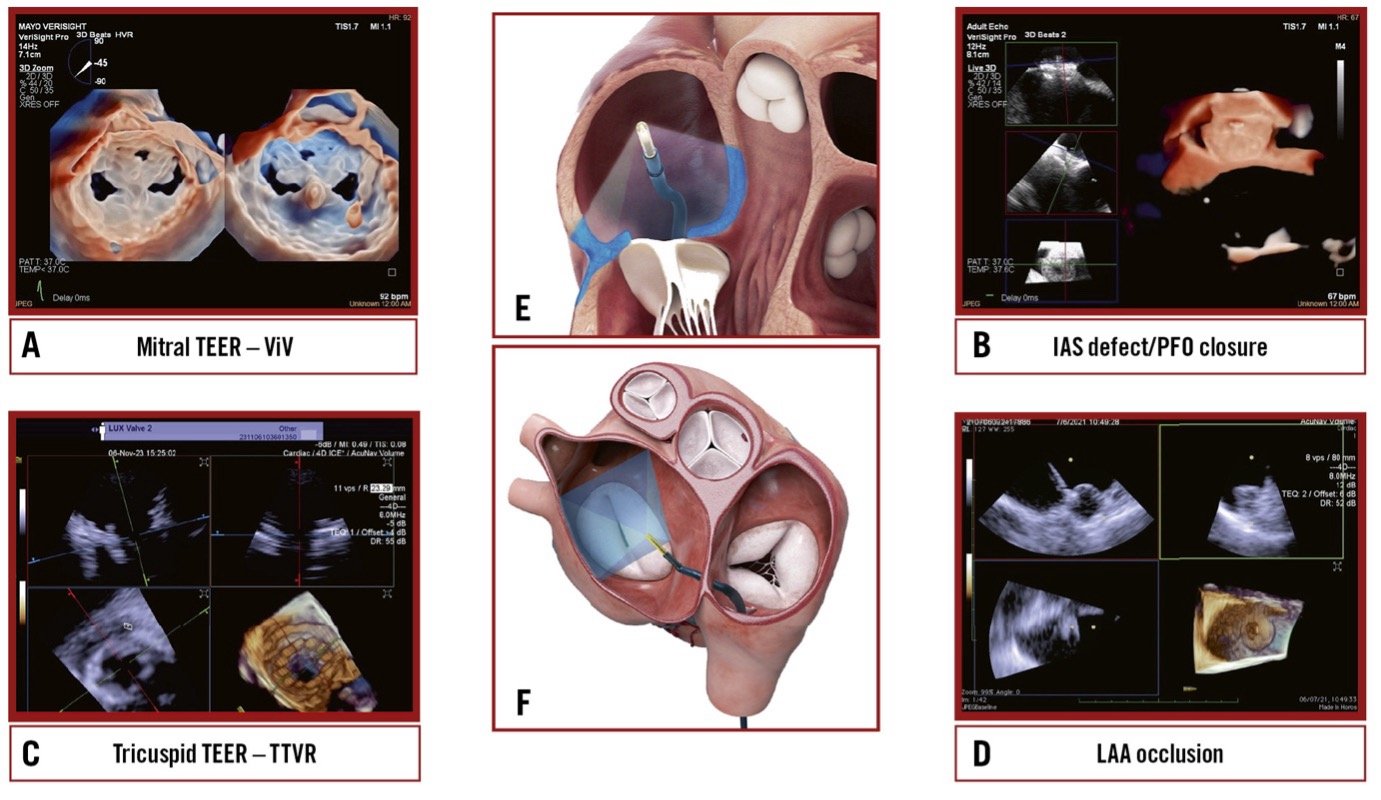

Evolving indications for edge-to-edge repair

This expert review examines the use of transcatheter mitral edge-to-edge repair (TEER) in patient populations beyond current indications, discussing the outcomes and limitations seen in these diverse patient groups.